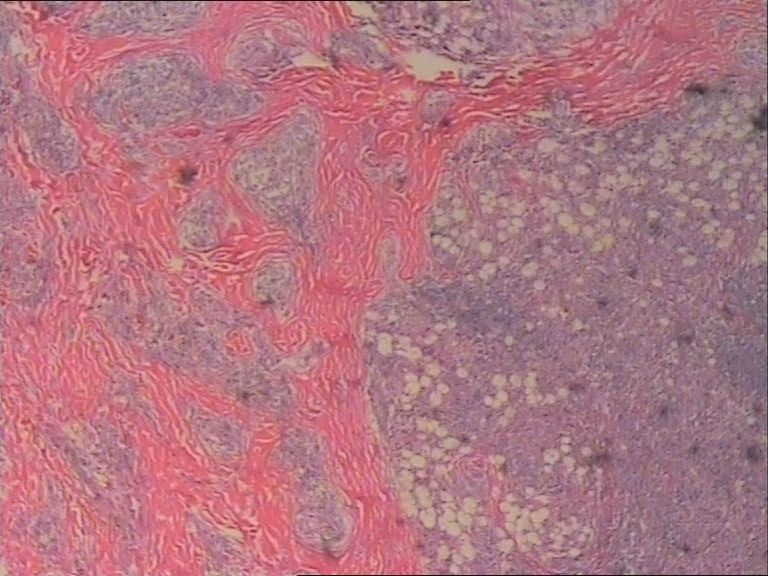

表皮下肿块FNAC一例,体现了该诊断手段的优势。

患者 女 47岁 腰部皮下肿块5x4cm,皮肤表面灰褐色,无隆起,无压痛。体格检查无其他异常。

诊断是Rosai-Dorfman病。

是的,单核及多核组织细胞是本病不特异但恒定的特点。

涂片内见较多组织细胞和多核巨细胞。肉芽肿性炎。